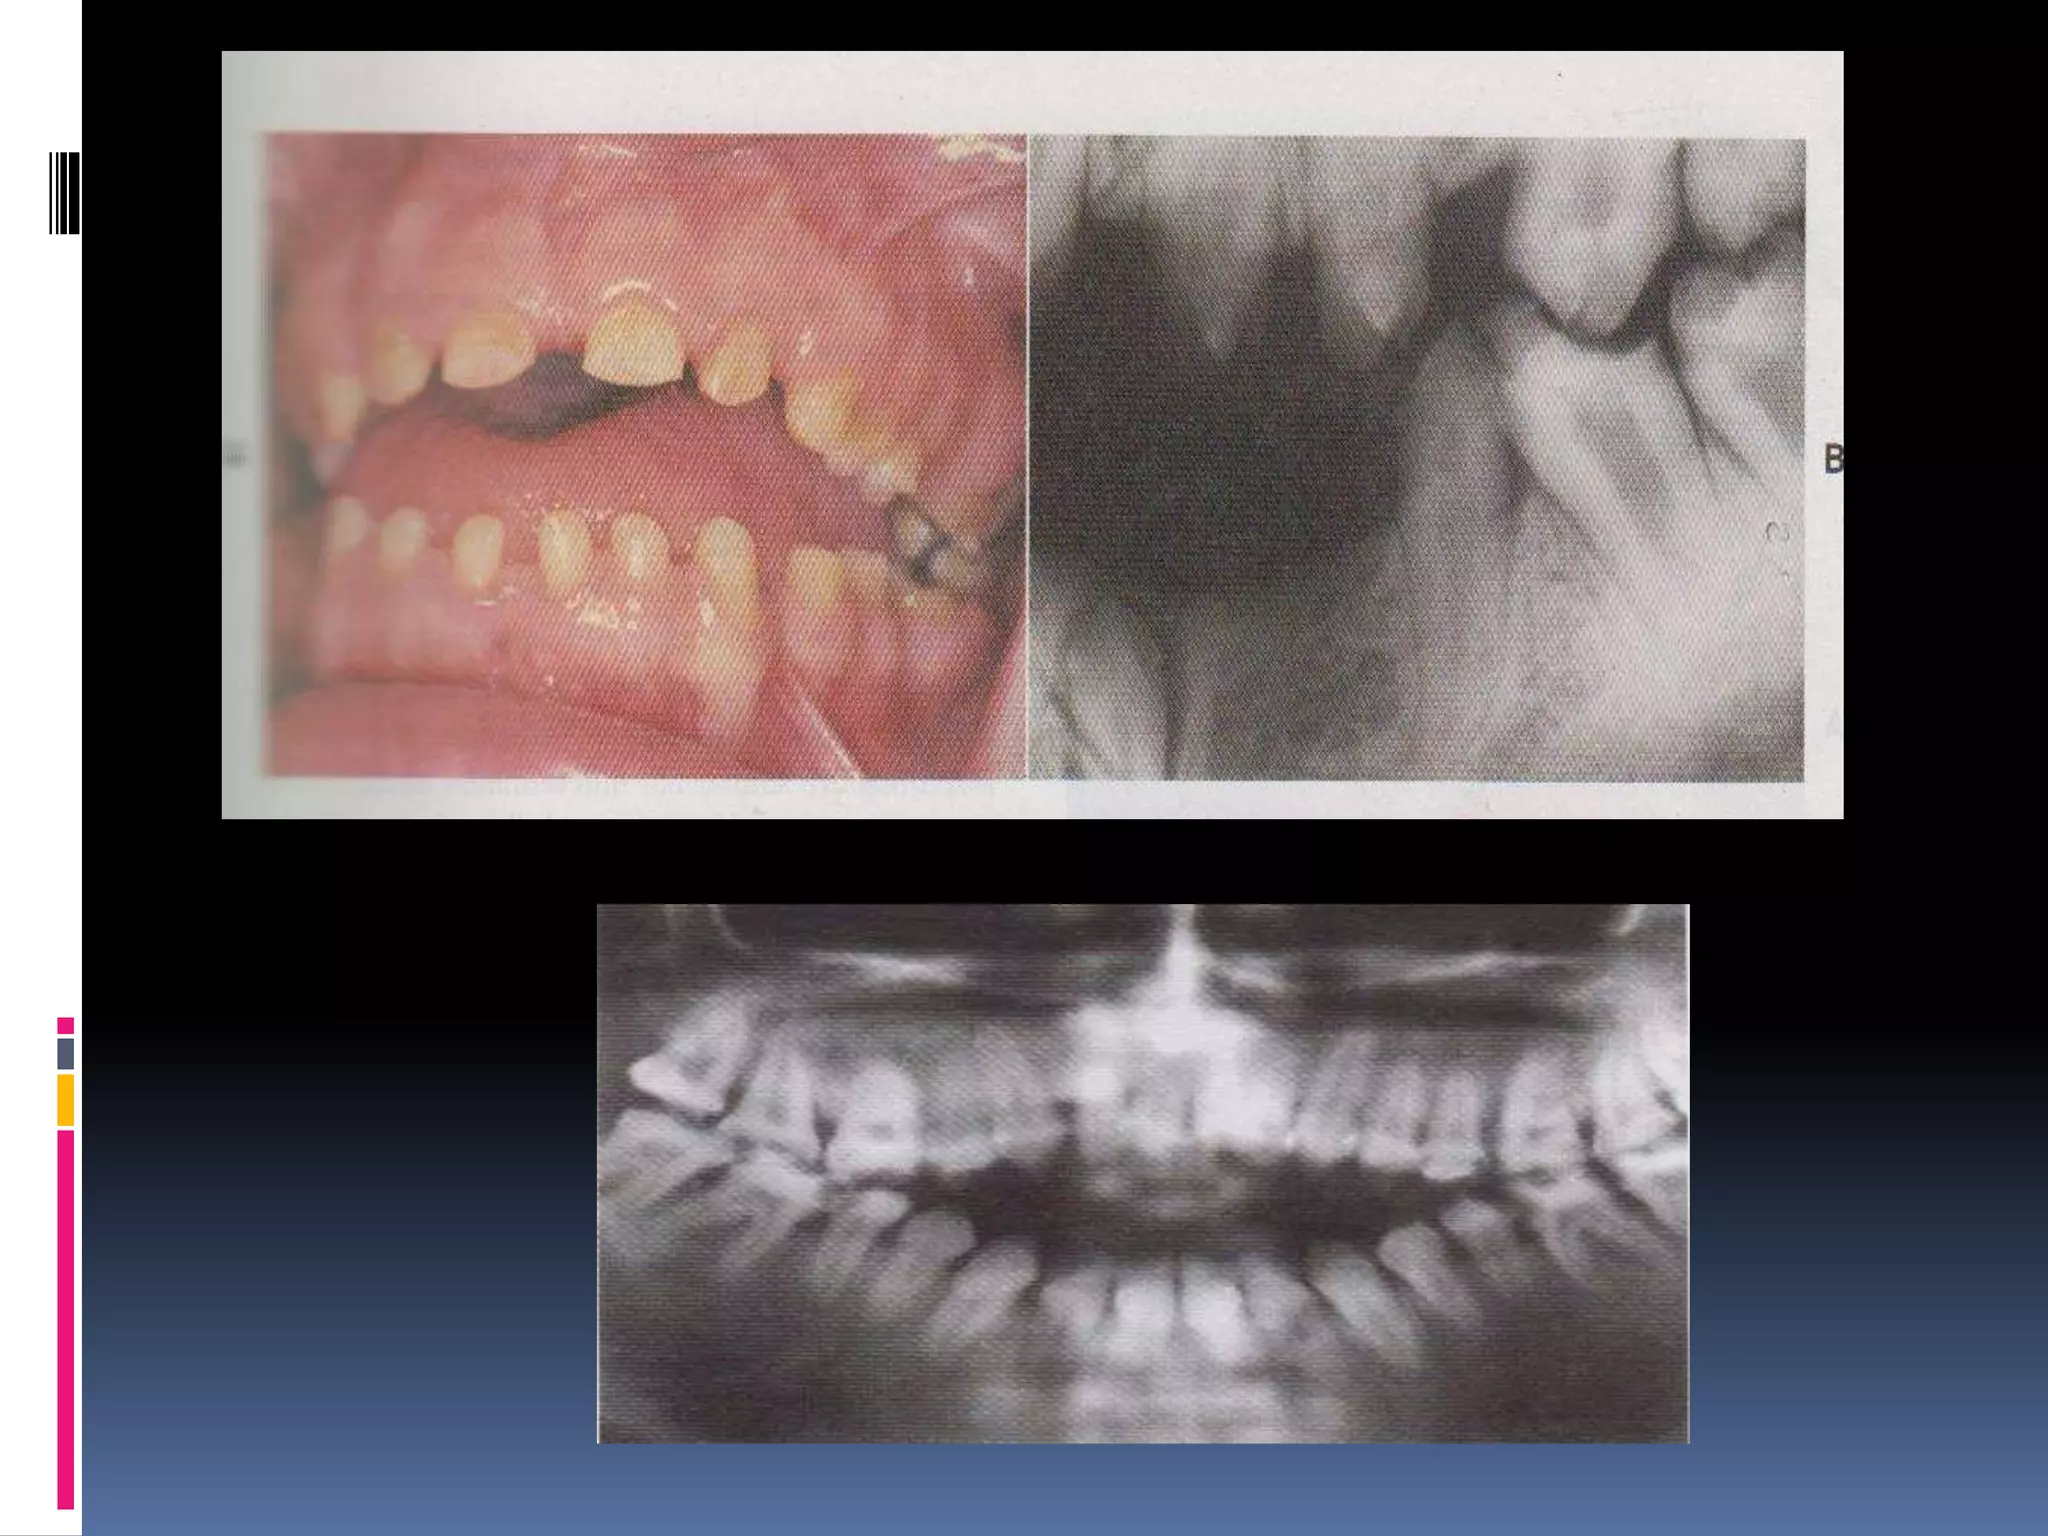

Radiology

 Panoramic radiographs